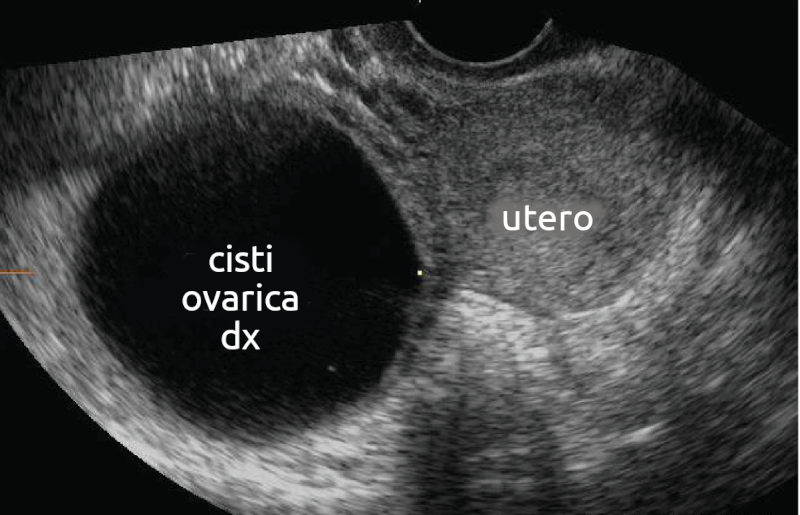

Cisti ovarica

- Descrizione: Cisti piena di liquido o di altro tessuto che si forma nell'ovaio. Solitamente benigne e inoffensive, scompaiono da sole il più delle volte, sebbene a volte possano causare problemi.